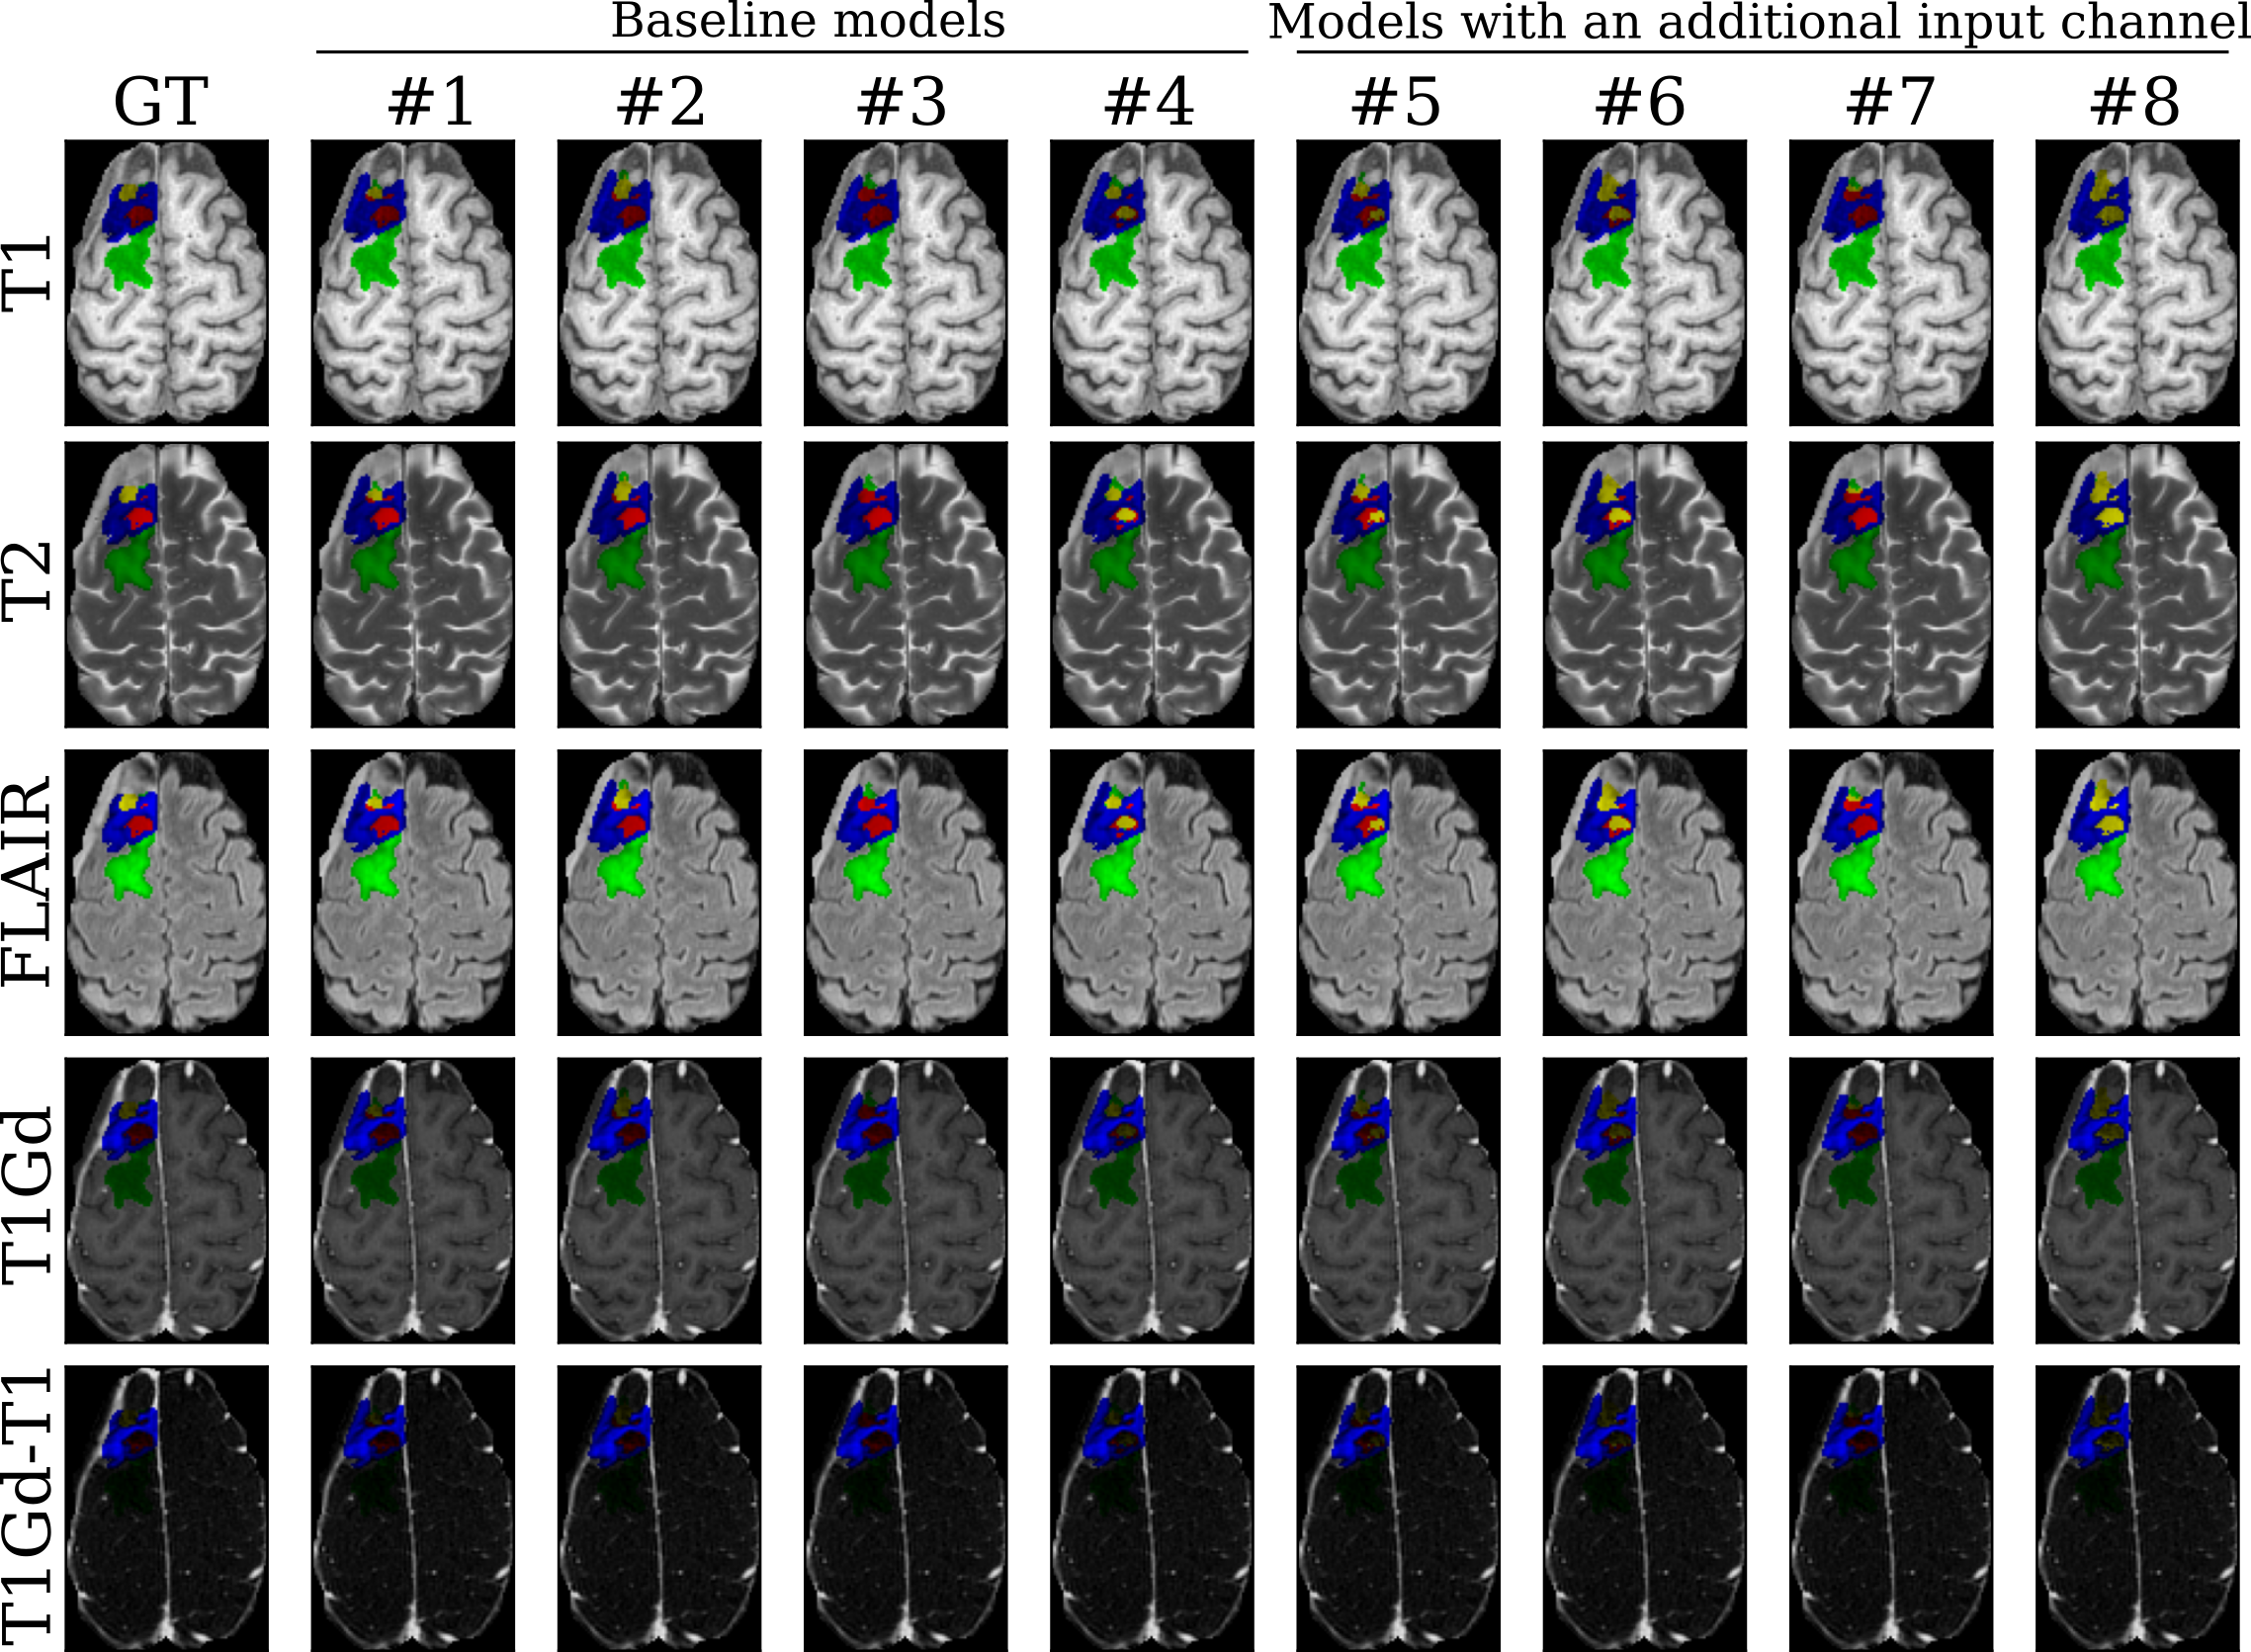

Figure 2: Segmentation results visualization on one subject in the internal validation set on the different MR imaging input modalities (lines). The ground truth annotation (GT) is compared against our baseline models (columns #1 to #4) and our models with the T1Gd-T1 input (columns #5 to #8). Labels include enhancing tissue (ET, blue), non-enhancing tumor core (NETC, red), surrounding non-enhancing FLAIR hyperintensity (SNFH, green), and resection cavity (RC, yellow).

For the internal validation set, we show results for LD and LH95 scores in Table 1 and Table 2. For index #1-4, we calculate LD and LH95 for each baseline with 4 input scans. For index #5-9, we calculate LD and LH95 with 5 input scans, including the additional T1Gd-T1 input scan. Figure 2 presents qualitative segmentation results for one subject in the internal validation set for the baseline models with (columns #1-4) and without (columns #5-8) including the additional T1Gd-T1 input scan against the ground truth annotations (GT). While both groups of models depict similar predictions for the SNFH label (green), we observe more accurate contours for the ET (blue) using the proposed additional input. For indices #9-11 and #12-14, we calculate STAPLE/weighted ensemble results with respect to the aforementioned baselines. We observe that for single baseline results, incorporating additional channel input generally improves LD scores. We also observe better LD and LH95 scores with larger baseline models (ResEncUNetL to ResEncUNetXL). For ensemble approaches, STAPLE and weighted average generally improve performance compared with single baselines. In Figure 3, we visualize qualitative segmentation results for one subject in the internal validation set for ensemble models using STABLE (columns #9-11) and the proposed weighted approach (columns #12-14) against the ground truth annotations (GT). For the selected subject, the STABLE ensemble models provide a better detection of the RC (yellow) while the proposed weighted ensemble models focus on accurate segmentation of the NETC (red).